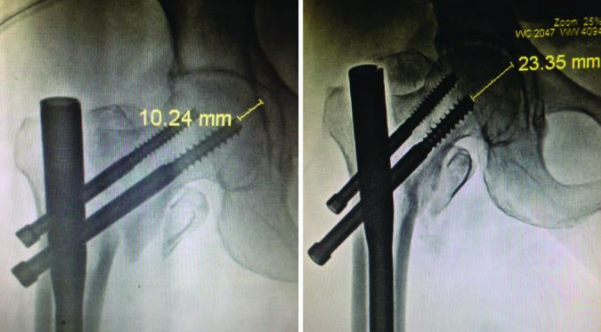

Tip-apex Distance: Both groups' average Tip Apex Distance (TAD) was substantially below the indicated safe range of 25 mm. The PFN group measured 19.08 mm (range 8.42-27.37 mm) and the PFNA group measured 21.13 mm (range 11.08-36.1 mm). The average TAD for cases of implant failure in the PFN group was 22.21 mm, but the TAD for the one patient with PFNA implant failure was 32.32 mm. There was no implant failure in seven other cases of TAD > 25 mm treated with the PFNA.

Complications in patients with Singh’s index ≤ 3: Three of the eight patients with considerable osteoporosis in the PFN group had implant failure, whereas none of the 13 patients with significant osteoporosis in the PFNA group had implant failure. This difference in complication rates was found to be significant (p=0.04) in the context of osteoporosis. Implant fracture, screw back out [Table/Fig-9], and Z effect were the problems encountered in these osteoporotic instances. The TAD and implant site were both optimal in the first two cases, and the Singh's grade was 3. The TAD for the Z-effect was 26.47 mm, and the Singh's grade was 2. Four patients with Singh's grade 3 had TAD > 25 mm in the PFNA group, but none of them suffered blade migration or failure.

Table/Figure 9: A case of back-out of the compression screw of a dual screw design over six weeks after initial fixation.